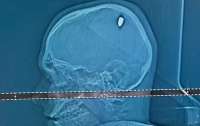

Бразильский студент четыре дня веселился на вечеринках с пулей в голове